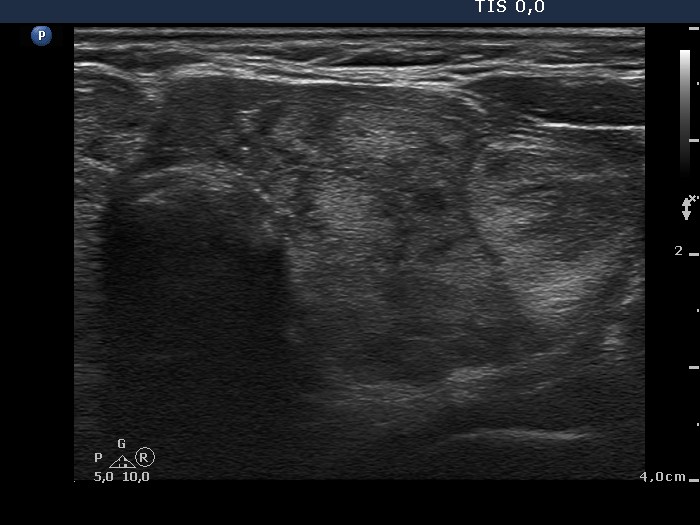

It is worth comparing the numerous small echonormal lesions and the large nodule in the left thyroid. The former are part of the so-called pseudonodular form of Hashimoto's thyroiditis, while the true nodule was much larger. Pseudonodules are usually in the range of 5 to 15 mm in maximal diameter.

This patient had a rare compression sign. We suppose that the nodule comprised a nerve while the patient turned her head to the right. This complaint was resolved after the surgery.

Most solitary nodules which are greater than 2 cm in maximal diameter, display a halo sign and perinodular blood flow are proved to be follicular tumor. This case belongs to the relatively rare exceptions.